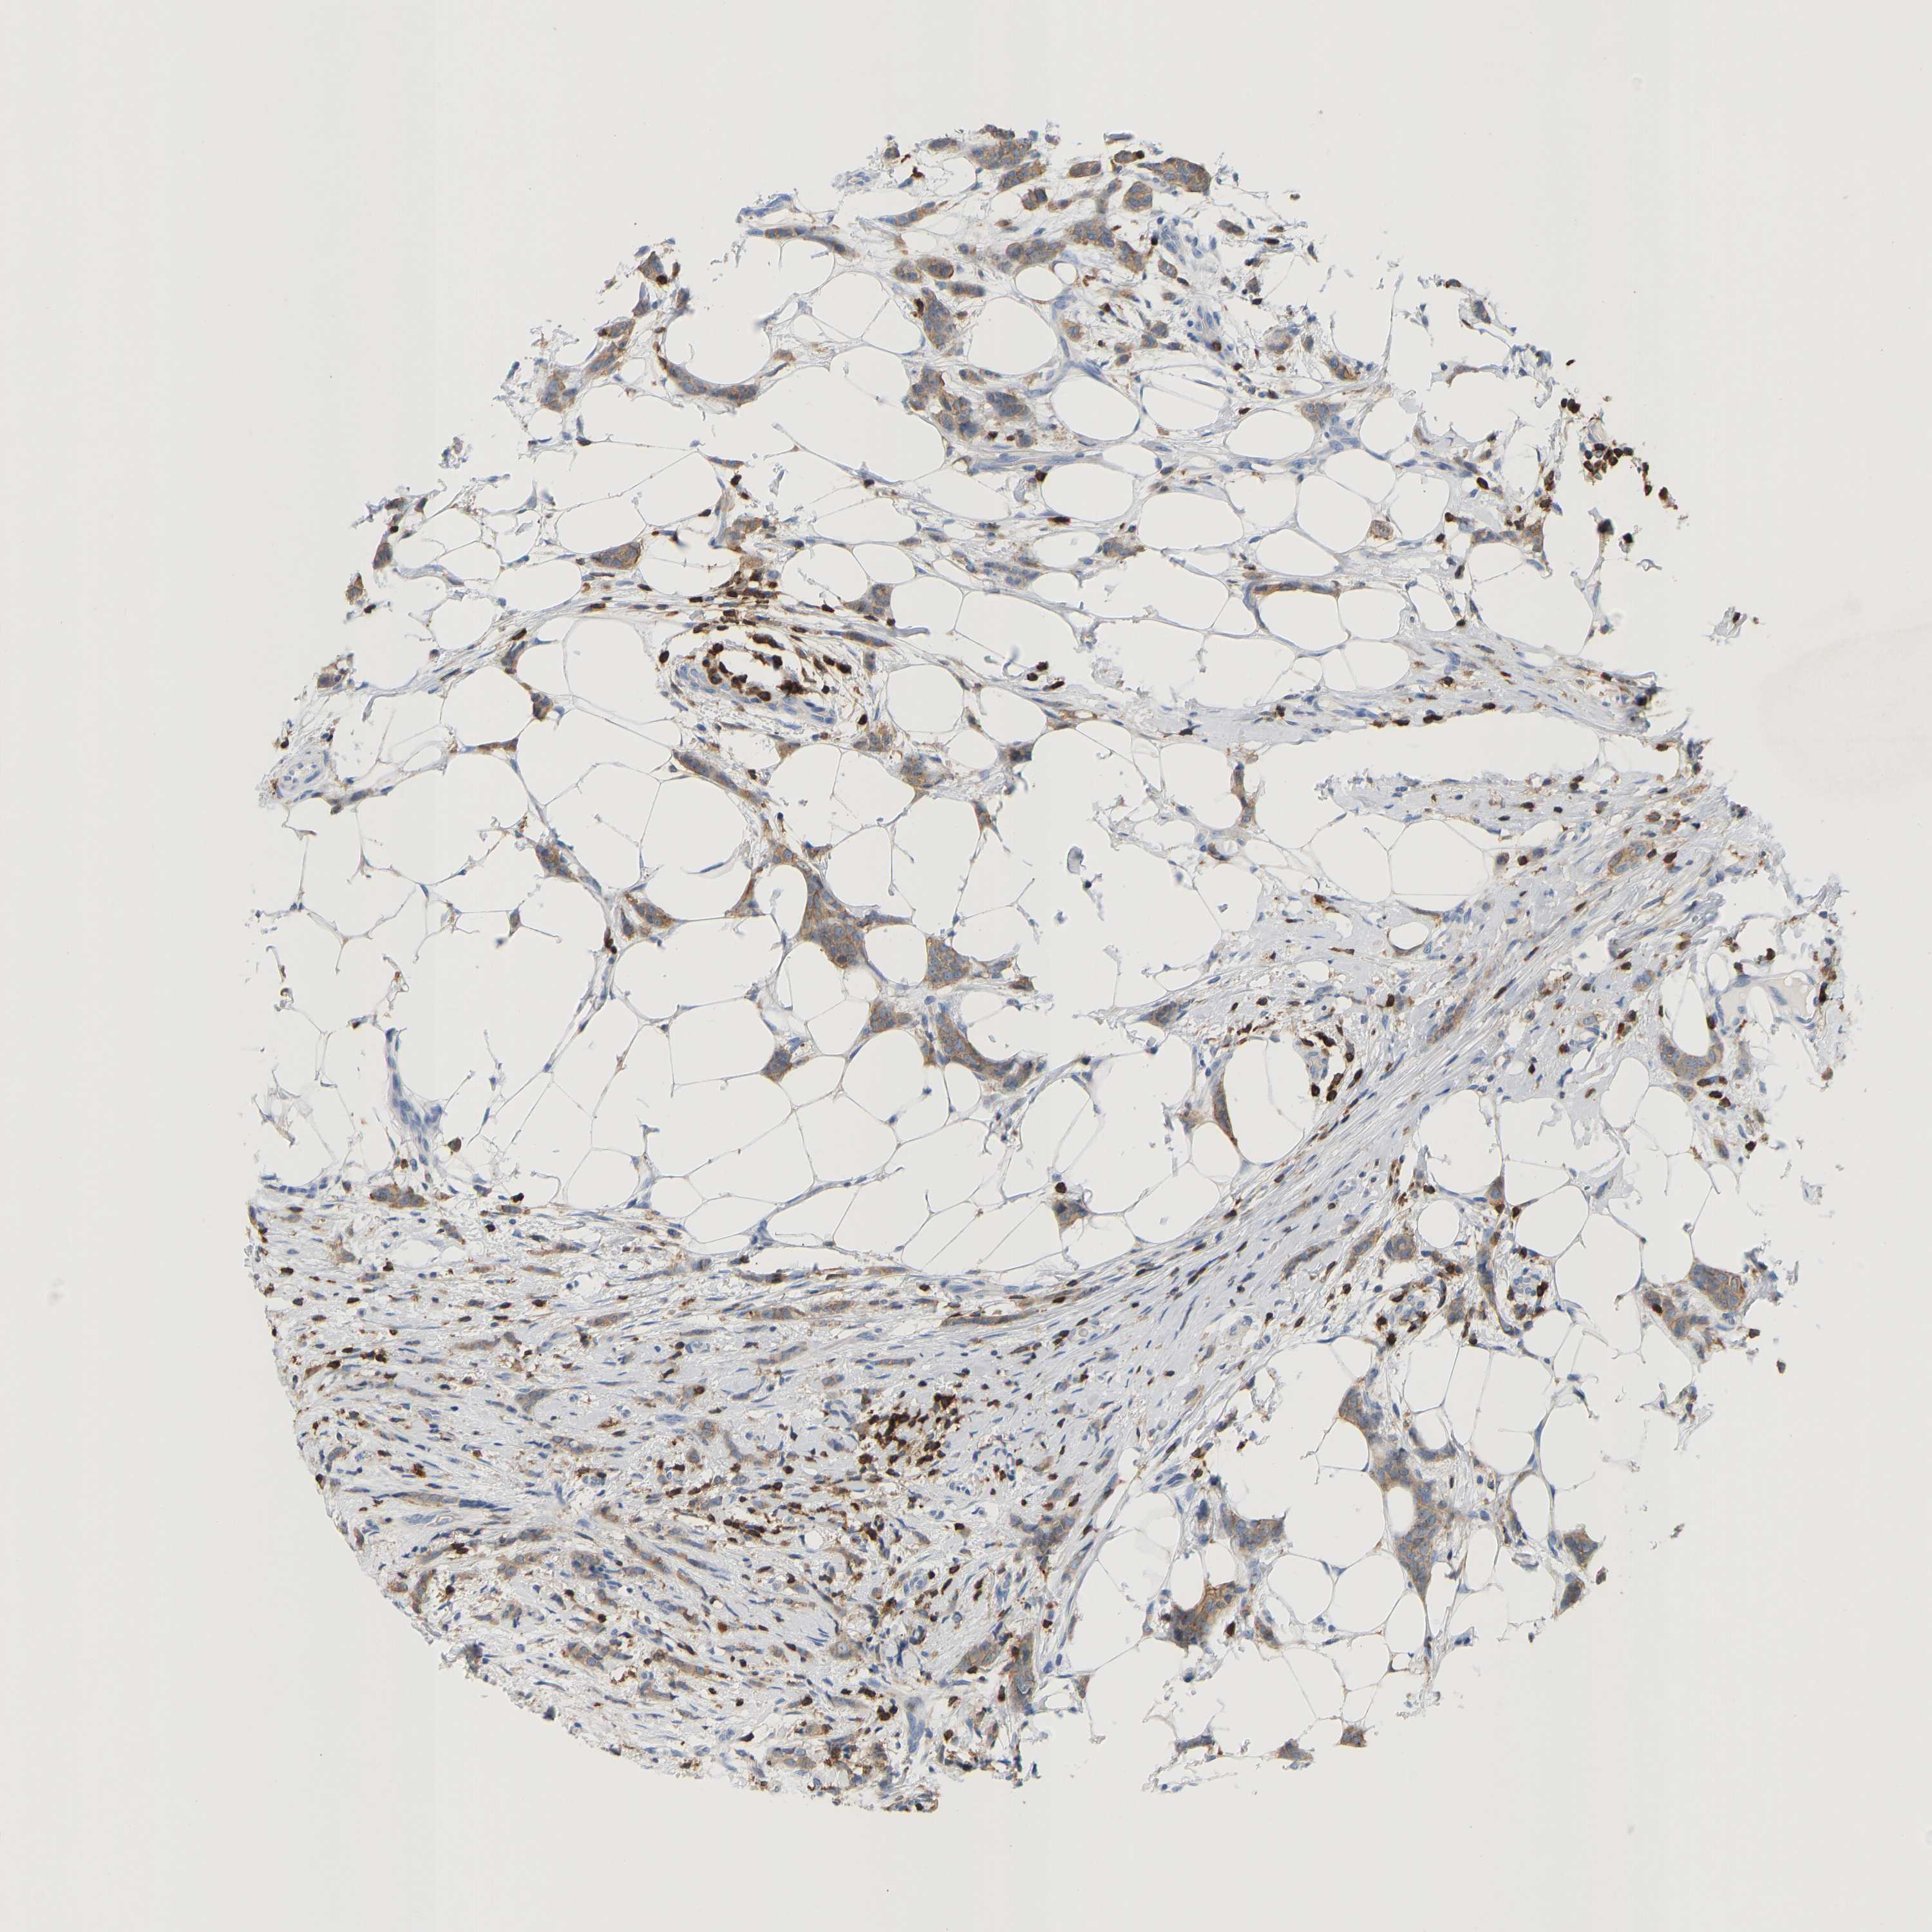

CANCER BREAST CANCER Show tissue menu

BRCA TCGA BRCA VALIDATION PROTEIN EXPRESSION

ANTIBODIES

AND

VALIDATION